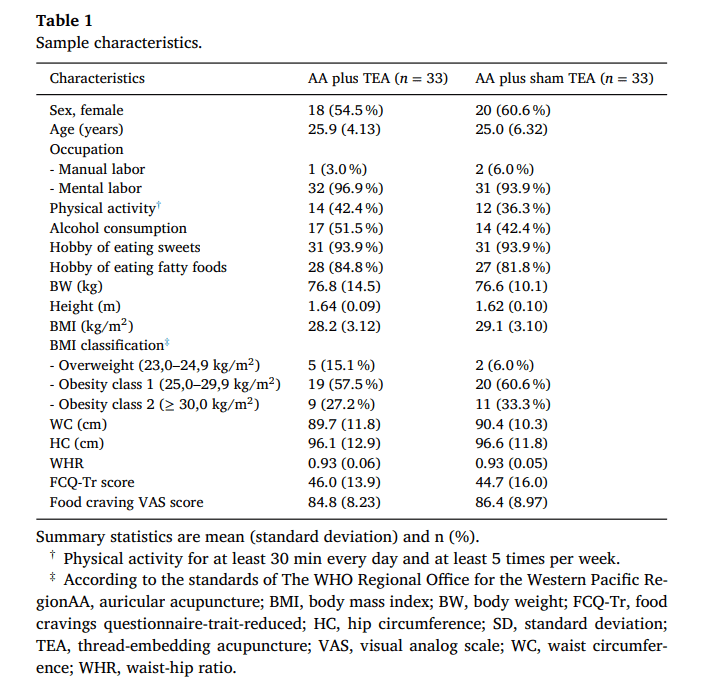

ویژگیهای نمونه

ویژگیهای دموگرافیک و بالینی پایه شرکتکنندگان تصادفیشده در جدول ۱ ارائه شده است. اکثریت شرکتکنندگان زن بودند، با میانگین سنی ۲۵ سال که عمدتاً در فعالیتهای ذهنی مشغول بودند.

- میانگین وزن بدن (BW) حدود ۷۷ کیلوگرم بود.

- میانگین BMI در گروه AA + TEA برابر با ۲۸.۲ و در گروه AA + TEA ساختگی برابر با ۲۹.۱ بود.

- اکثریت شرکتکنندگان در طبقهبندی چاقی قرار داشتند.

بهطور کلی، ویژگیهای پایه بین دو گروه بهطور یکنواخت توزیع شده بود.

آمار خلاصه بهصورت میانگین (انحراف معیار) و تعداد (%) ارائه شده است.

- † فعالیت بدنی حداقل ۳۰ دقیقه در روز و حداقل ۵ بار در هفته.

- ‡ طبق استانداردهای دفتر منطقهای سازمان جهانی بهداشت در غرب اقیانوس آرام.

- AA: طب سوزنی گوش | BMI: شاخص توده بدنی | BW: وزن بدن | FCQ-Tr: پرسشنامه ولع غذایی | HC: دور باسن | SD: انحراف معیار | TEA: طب سوزنی کاشت نخ | VAS: مقیاس بصری ولع غذایی | WC: دور کمر | WHR: نسبت دور کمر به دور باسن.